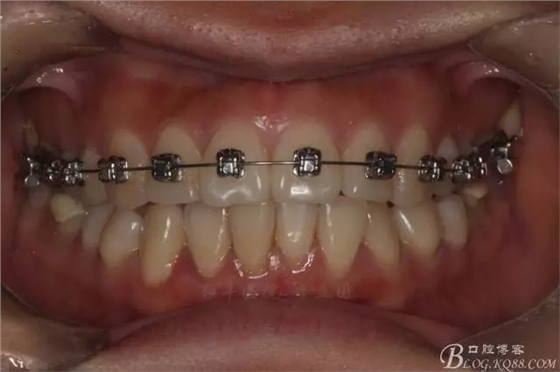

如圖,該病例為簡(jiǎn)單排齊病例,但77鎖合是矯治中的關(guān)鍵所在,你會(huì)怎么處理?

該病例主要為17、27頰側(cè)位同時(shí)伴有伸長(zhǎng),當(dāng)然種植支抗可以解決,但還有簡(jiǎn)單實(shí)用的辦法嗎?如圖,在橫腭桿遠(yuǎn)中延伸出牽引鉤,位置盡量遠(yuǎn)離合平面,7粘舌側(cè)扣,牽引力的方向?yàn)閴旱图吧嘞?,下圖為兩個(gè)月的效果,17已到位,27還未到位。